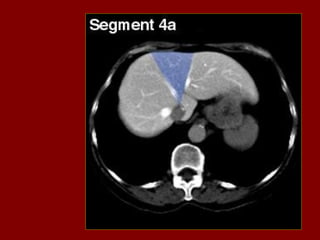

INCISÃO SOBRA AVEIA HEPÁTICA DIREITA

INCISÃO SOBRE AVEIA HEPÁTICA MÉDIA.

INCISÃO SOBRE AVEIA HEPÁTICA ESQUERDA.